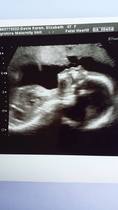

looking good catface!!!

this is my bump pic at 21+4 and also our scan picture yayyyyyyy